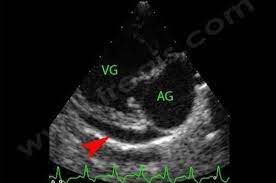

Pericardites Et Epanchement Pericardique Chez Le Chien Centre Hospitalier Veterinaire Fregis

visitez l'article complet ici : https://www.fregis.com/infos-sante/pericardite-epanchement-pericardique-chez-chien/

Pericardite Wikipedia

visitez l'article complet ici : https://fr.wikipedia.org/wiki/P%C3%A9ricardite